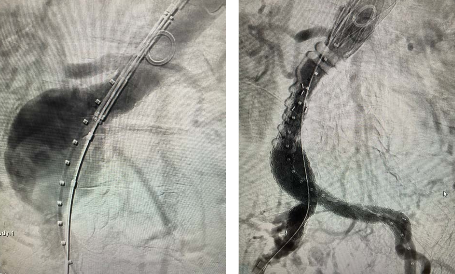

We completed the first 2 perc bypass in Illinois w #Detour @endologix Excited for this groundbreaking technology to be in the hands of #limbsalvage docs around the globe. @ShawnPenn33 @DeanFerreraDO @Abd_Alrifai @MarcoShaker @tlevin @advocatehealth